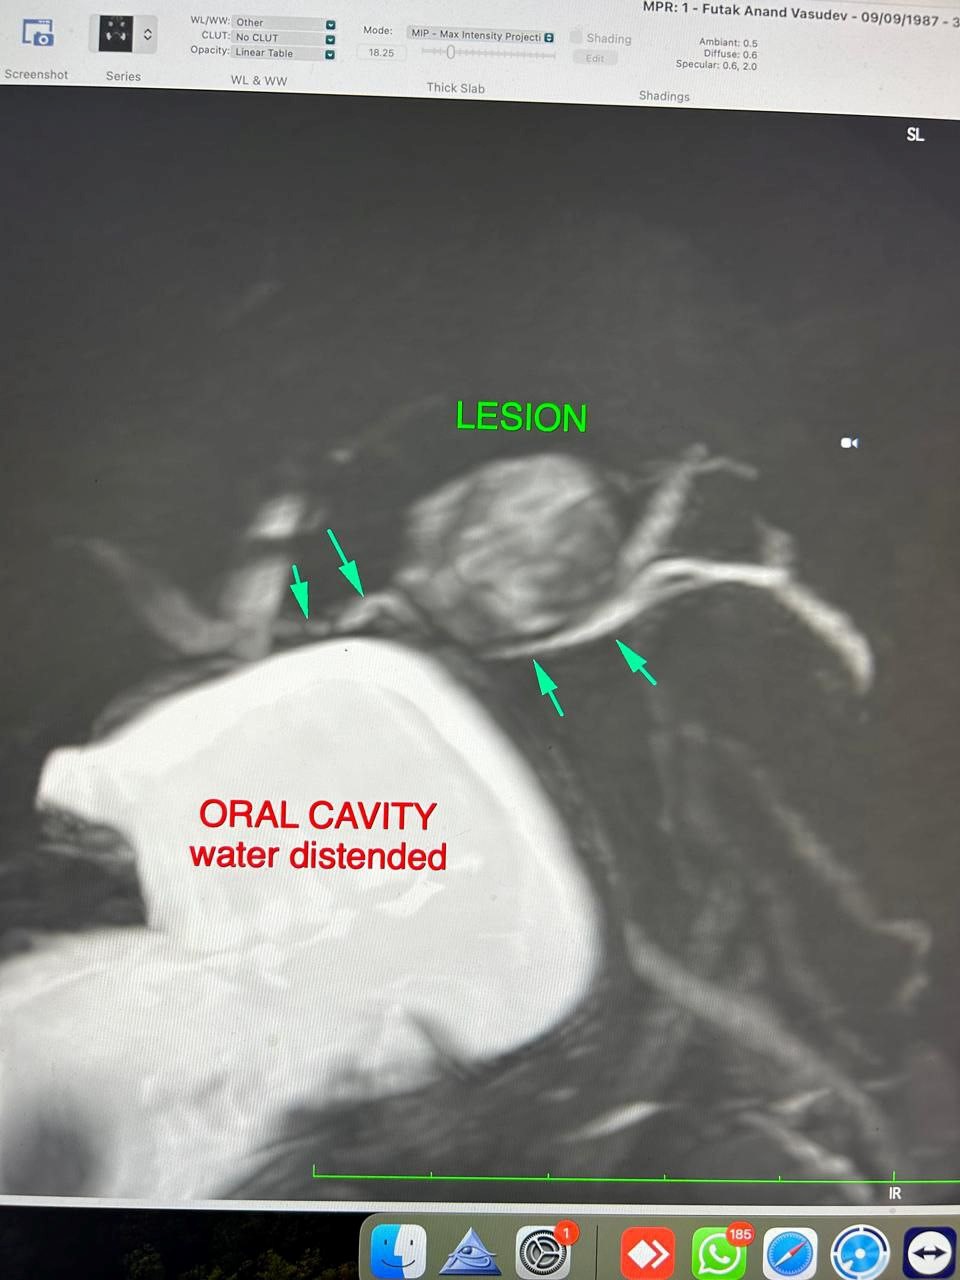

MRI (Neck and Parotid Gland):

A well-defined ovoid lesion measuring 2.0 × 1.6 × 1.3 cm in the left cheek region, hypointense on T1 and heterogeneously hyperintense on T2-weighted images with few cystic foci. The lesion arose exophytically from the anterior portion of the left parotid gland, deep to the buccinator and superficial to the anterior masseter. The parotid duct was displaced inferomedially but remained patent with no proximal dilatation. No deep lobe extension or perineural spread was observed.

Impression: Imaging features consistent with pleomorphic adenoma.